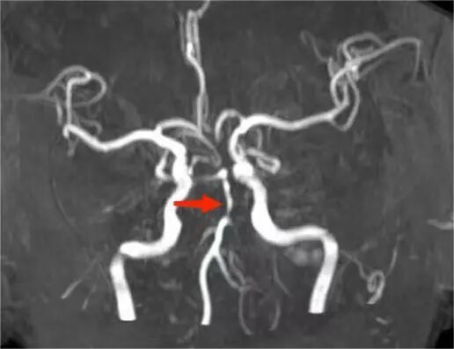

家属发现老人突发意识不清后没有丝毫迟疑,凭借对脑梗死急救知识的了解,立即将老人送往西安市第三医院,抵达医院时,老人意识已呈浅昏迷状,病情危重。神经内科第一时间启动卒中绿色通道,急诊头颅CT、MR检查迅速完成,提示左侧椎动脉颅内段、基底动脉管壁异常,考虑脑梗死。幸运的是,因送医及时,MR梗死灶尚未显影,为溶栓治疗争取到宝贵时机。